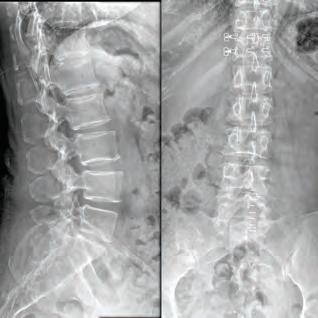

Stephen P. Courtney, MD

BOARD-CERTIFIED, FELLOWSHIP-TRAINED ORTHOPEDIC SPINE SURGEON PRACTICING FOR 26 YEARS.

For board-certifid, fellowship trained orthopedic spine surgeon

Dr. Stephen P. Courtney, patients come fist. It’s an ethos that developed early on in his life and one that has helped guide him in his journey to earn a distinguished reputation among his professional colleagues, medical peers and, most importantly, his patients.

Dr. Courtney’s residency at Texas A&M University Medical Center and further specialty training through a fellowship at Florida Neck & Back Institute in Gainesville, Florida, additionally cemented his strong medical foundation. From there, he continued to gain more knowledge and insight on how to help his patients with useful tools, while recognizing there was room for much improvement in the tools at hand.

Ths realization inspired Dr. Courtney to design, develop, biomechanically test, complete FDA testing and oversee quality control and

validation on a host of tools he created. To date, Dr. Courtney has developed nine spinal product lines and obtained nine patents and 14 trademarks on spine related products.

When he’s not traveling the country training other physicians on how to utilize his products, Dr. Courtney dedicates himself to the patients of his own medical practice, Advanced Spine Center.

Led by Dr. Courtney, the skilled team at Advanced Spine Center cares for patients with neck and back pain using a wide array of the most state-of-the-art tools and techniques—from conservative physical therapy and injection therapy—to advanced pain management, as well as surgical intervention. We employ the latest in minimally invasive spine surgeries, in addition to cutting-edge replacement technology. Incorporating both high tech and high touch, we get our valued patients back to their lives so they can enjoy all the activities they love.